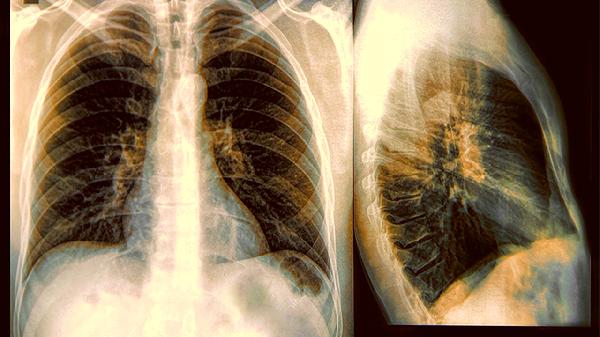

變異性哮喘通常分為急性發(fā)作期、慢性持續(xù)期、臨床緩解期和終末期四個階段。變異性哮喘是一種特殊類型的哮喘,主要表現(xiàn)為咳嗽、胸悶、喘息等癥狀,病情可能隨著時間推移逐漸加重。

變異性哮喘的四個階段

1、急性發(fā)作期

急性發(fā)作期是變異性哮喘癥狀突然加重的階段,患者可能出現(xiàn)劇烈咳嗽、呼吸困難和喘息。這一階段通常由過敏原暴露、呼吸道感染或冷空氣刺激等因素誘發(fā)。急性發(fā)作期的治療重點(diǎn)在于快速緩解癥狀,常用藥物包括短效β2受體激動劑和糖皮質(zhì)激素。患者應(yīng)避免接觸已知的誘發(fā)因素,保持環(huán)境清潔,減少過敏原暴露。

2、慢性持續(xù)期

慢性持續(xù)期是變異性哮喘癥狀持續(xù)存在的階段,患者可能長期存在咳嗽、胸悶等不適。這一階段需要長期規(guī)律用藥控制癥狀,常用藥物包括吸入性糖皮質(zhì)激素和長效β2受體激動劑?;颊邞?yīng)定期監(jiān)測肺功能,評估病情控制情況。慢性持續(xù)期的管理目標(biāo)是減少急性發(fā)作頻率,維持正常肺功能。

3、臨床緩解期

臨床緩解期是變異性哮喘癥狀得到控制的階段,患者可能無明顯不適癥狀。這一階段仍需繼續(xù)維持治療,防止病情反復(fù)。患者應(yīng)遵醫(yī)囑調(diào)整藥物劑量,不可擅自停藥。臨床緩解期的重點(diǎn)是預(yù)防急性發(fā)作,保持良好的生活習(xí)慣,避免誘發(fā)因素。

4、終末期

終末期是變異性哮喘病情嚴(yán)重且難以控制的階段,患者可能出現(xiàn)持續(xù)性呼吸困難和生活質(zhì)量顯著下降。這一階段需要綜合治療措施,包括高劑量藥物治療、氧療等。終末期患者應(yīng)定期隨訪,評估病情進(jìn)展,必要時考慮生物靶向治療。終末期管理的重點(diǎn)是改善癥狀,提高生活質(zhì)量。

變異性哮喘患者應(yīng)保持規(guī)律作息,避免接觸過敏原和刺激物,注意保暖防寒。飲食上應(yīng)均衡營養(yǎng),適量補(bǔ)充維生素和礦物質(zhì),避免食用可能誘發(fā)過敏的食物。適當(dāng)進(jìn)行有氧運(yùn)動有助于改善肺功能,但應(yīng)避免劇烈運(yùn)動?;颊邞?yīng)定期復(fù)診,監(jiān)測病情變化,遵醫(yī)囑調(diào)整治療方案。保持良好的心理狀態(tài)對病情控制也很重要,必要時可尋求心理支持。